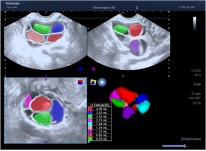

10. 全面的心脏应用:Aplioi900可为临床提供全方位心脏超声解决方案,支持专业的经胸心脏探头及经食道探头。

1) 二维/三维室壁运动追踪技术 (2D/3D Wall Motion Tracking)

2) 心脏容积成像